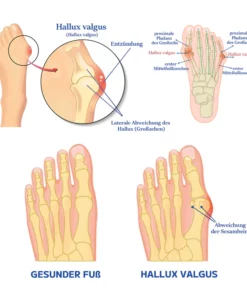

Was ist ein Ballenzeh?

Ein knöcherner Knubbel, bekannt als Hallux valgus, bildet sich an der Basis des Großzehengelenks. Dies geschieht, wenn einige der Knochen im Vorderfuß aus der Ausrichtung rutschen. Das Gelenk an der Basis des großen Zehs wird gezwungen, hervorzustehen, weil die Spitze des großen Zehs zu den kleineren Zehen gezogen wird. Über dem Hallux valgus kann es zu Schmerzen und Entzündungen kommen.

Hallux valgus oder Ballen betreffen etwa 30% der Bevölkerung. Sie entstehen durch die Fehlstellung von Metatarsal- und Phalanxknochen im Fuß, was zu einer Entzündung und Vorwölbung des Gelenks führt. Genetik, Fußverletzungen, die die Knochenstruktur verändern, und schlecht sitzende Schuhe tragen zur Bildung von Ballen bei. Diejenigen mit einer erblichen Veranlagung, flachen Bögen oder einer Vorgeschichte von Fußverletzungen sind anfälliger. Enge oder hochhackige Schuhe erhöhen das Risiko. Ballen können unbehandelt im Laufe der Zeit schlimmer werden und Unannehmlichkeiten und Schmerzen verursachen.